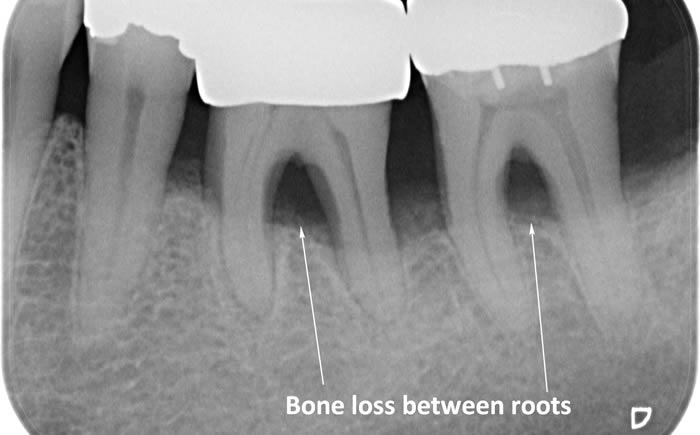

Periodontitis is a more advanced stage of gum disease where there has been damage to the bone which supports the teeth. If left untreated periodontitis leads to more and more bone loss until the teeth start to become loose and eventually fall out by themselves or need to be extracted by a Dentist.

The main cause of gum disease is plaque. Plaque consists of millions of bacteria which live on and around the teeth and gums. These bacteria produce toxins which damage the gums. To begin with the gums start to peel away from the teeth and “pockets” form. As the bacteria penetrate deeper into these “pockets” they then start to cause damage to the bone which holds the teeth in. As more bone loss occurs the teeth start to become increasingly looser until they eventually start to fall out one by one.

The diagrams below show the different stages of gum disease

In cases of advanced gum disease our Hygienist’s will also carry out deep scaling which cleans the root surfaces beneath the gum level. When pockets develop in the gums around the teeth plaque bacteria and calculus form on the root surfaces of the teeth and are protected from toothbrushing by the overlying gum. However, our Hygienist’s have special thin scaling instruments which can go down inside the pockets to clean the root surfaces. This treatment is carried out in small sections under local anaesthetic to ensure that you are comfortable throughout the treatment.